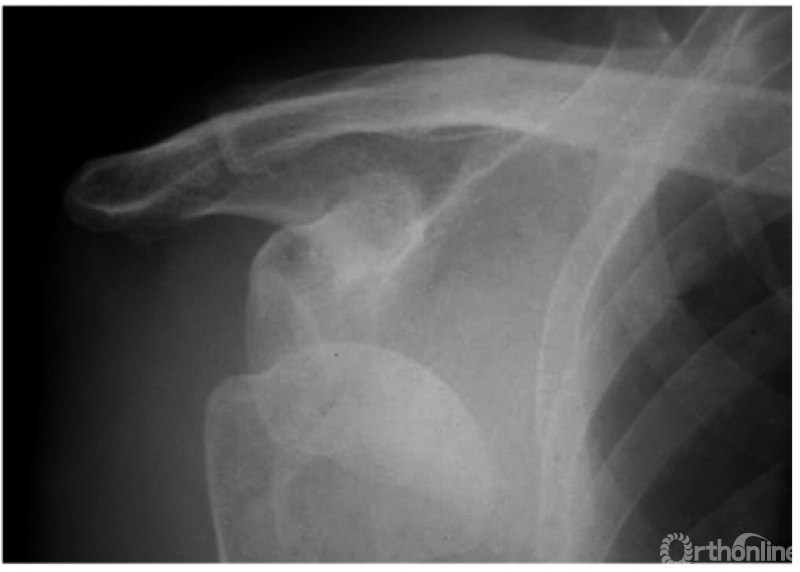

例1:肩关节盂下脱位(如下图)。

例2:希-萨(Hill-Sachs)二氏损伤。肱骨头后外侧劈裂骨折形成楔形缺损,骨折块下移并肩关节喙突下脱位(如下图)。